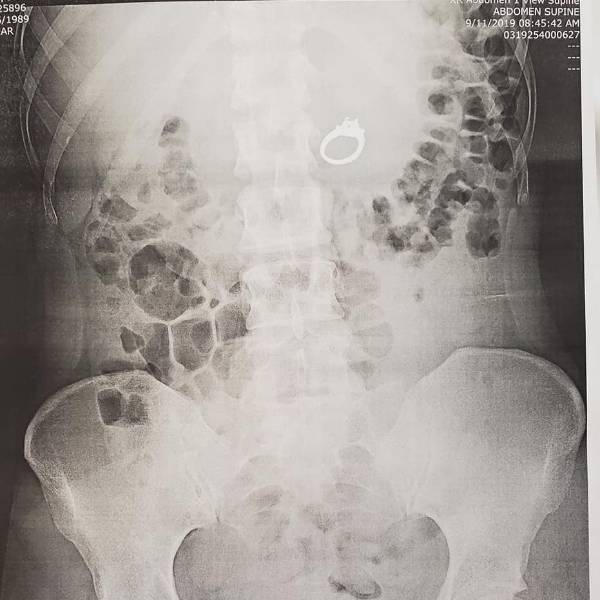

Jenna Evans se sometió a una intervención médica después de tragarse su anillo de compromiso mientras dormía, en California, Estados Unidos.

Mediante a una endoscopia digestiva oral, los médicos pudieron retirar el anillo de los intestinos de Evans. “Encontraron el anillo en mis intestinos, lo recuperaron y se lo dieron a Bobby, no a mí”.